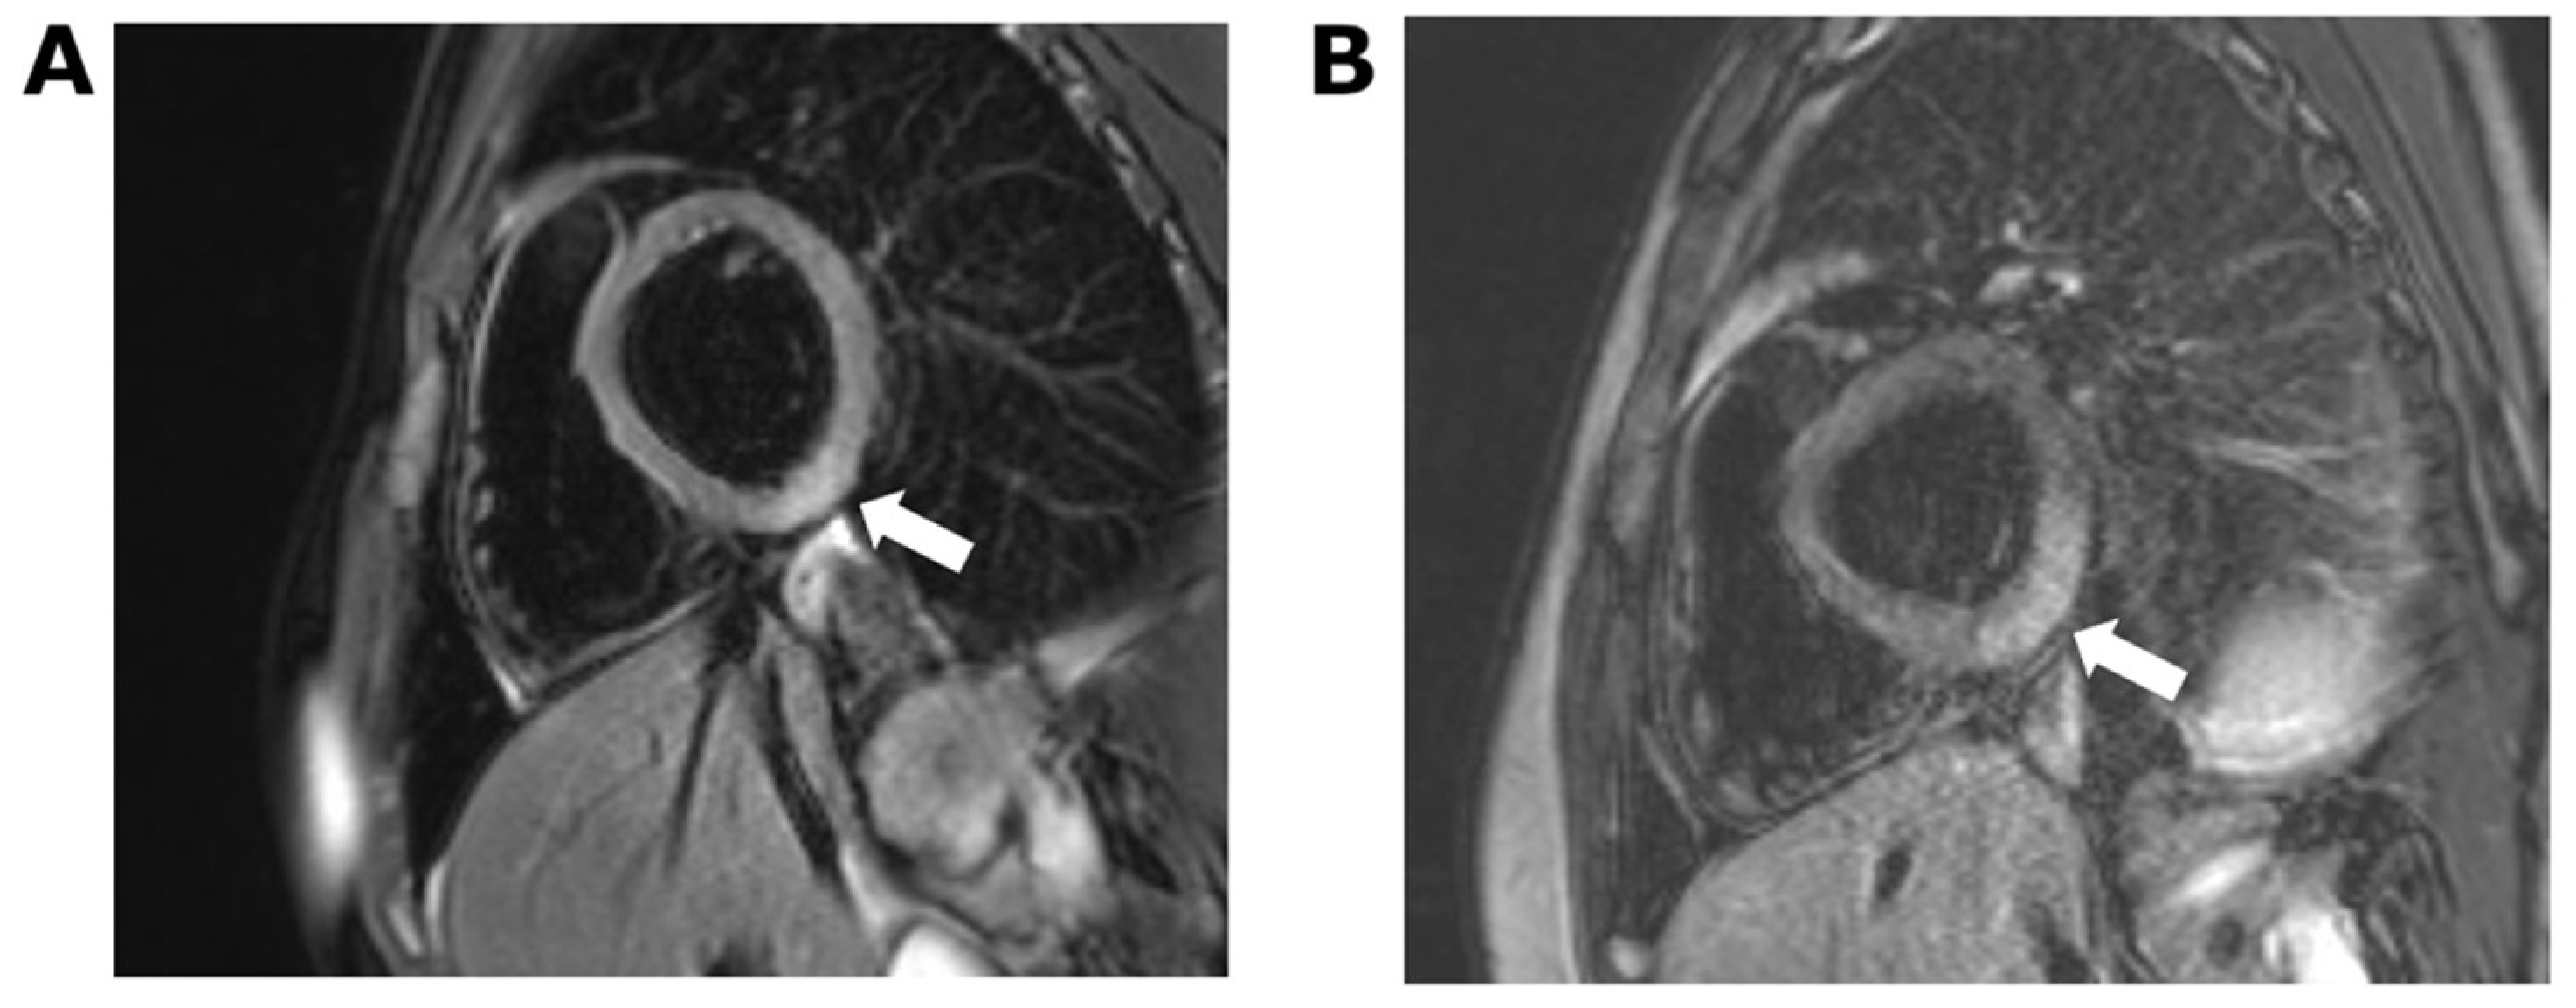

2. Case 1